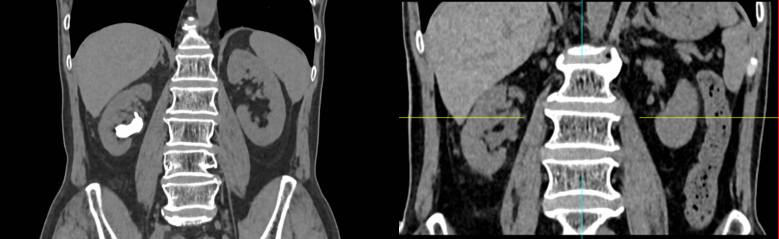

患者为62岁男性,影像学显示右肾存在不完全鹿角型结石,结石体积大、形态复杂,占据多个肾盏。按照传统方案,此类患者往往需要多通道经皮肾镜或分期手术,并常规留置肾造瘘管和输尿管支架,以确保引流安全,但部分患者术后疼痛明显、恢复时间较长、生活质量受影响,还需携带输尿管支架1月后返院拔除。

泌尿结石外科主任、主任医师舒建平与主任医师全科立于1月16日为患者实施手术,术中通过精准穿刺建立单一经皮通道,在低压灌注和高清内镜引导下,分区击碎并取出结石,减少了对肾实质的损伤。术中对出血、肾盂内压力和残余结石情况进行动态评估,确认引流通畅、出血可控、结石清除可靠后,果断实施“完全无管化”——即不放置肾造瘘管和输尿管支架,仅皮肤小切口一针缝合。

患者术后生命体征平稳,术第一天即拔除导尿管下床活动,无明显腰痛及血尿。复查影像提示肾形态良好,无血肿征象,术后第三天即康复出院,达到了“清石效果好、创伤更微小、恢复更快速”的综合治疗目标。